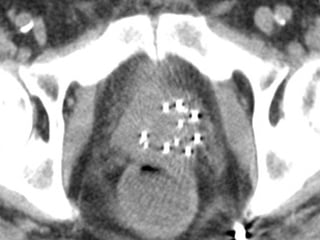

MRI Impacting Management 65 yr old, PSA 5, one core positive for Gleason 6 (right)  MRI: Large tumor in right anterior prostate with gross extra- capsular extension • Trigger for intervention/targeted biopsy

Missed significant cancersare usually anterior WHY: TRUS biopsy usually directed posteriorly Evidence: RPs performed on surveillance candidates MRI findings 02/23/13

•48/450 men onsurveillance having RP •65% OC •16/450 (5% of cohort) had non organ- confined disease at RP) •100% with tumor volume > 1.0 cm were anterior 02/23/13

•Negative predictive value for‘clinically significant’ PCa 95-98%